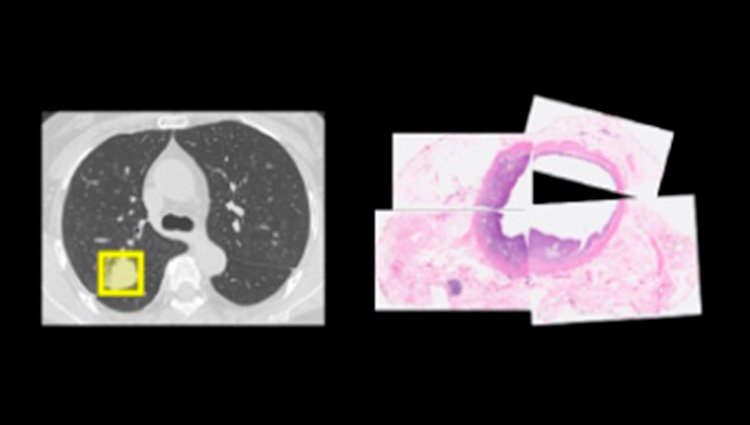

- Mejora de imagen

- Segmentación de la anatomía

- Detección / Diagnóstico

- Soporte de flujo de trabajo